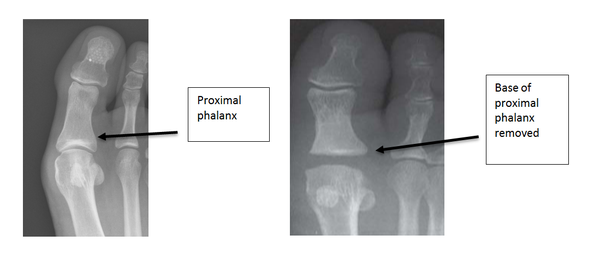

Arthroplasty

This procedure reduces the function of the big toe and can lead to weight transferring to the smaller foot joints. It has the advantage of providing some motion at the joint although the toe post-surgery is significantly shorter. This procedure is generally reserved for patients who have low levels of activity and require a short recovery time. Half of the arthritic joint is removed by resecting the base of the proximal phalanx. The operation should take away the joint pain but can leave the big toe shorter and not as stable on the ground.